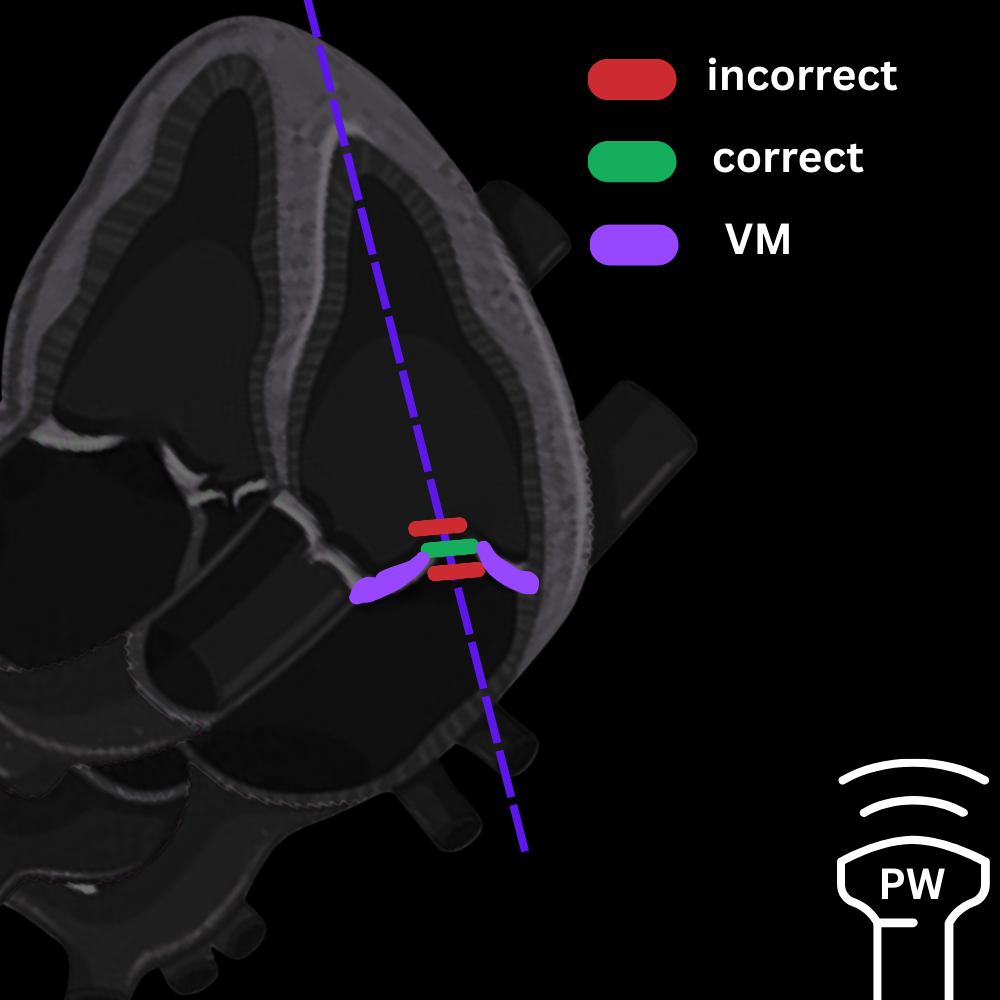

En A4C :

- Centrer la vue sur la valve mitrale

- Placer le curseur juste sous les feuillets mitraux (cf. photo ci-dessous)

- Activer le Doppler pulsé (PW)

- Obtenir les deux ondes du remplissage : onde E (remplissage précoce) et onde A (contraction atriale)

- Mesurer les pics de vitesse de E et A.

- Calcul automatique du rapport E/A.

- En A4C, placer le curseur sur l’anneau mitral, en latéral

- Activer le mode Doppler tissulaire (TDI).

- Chercher la premiere onde négative apres le onde S' – c'est l'onde E’ (cf. vidéo/photo ci-dessous)

- Mesurer la vitesse maximale de E’. La machine fait le calcul du rapport pour vous.